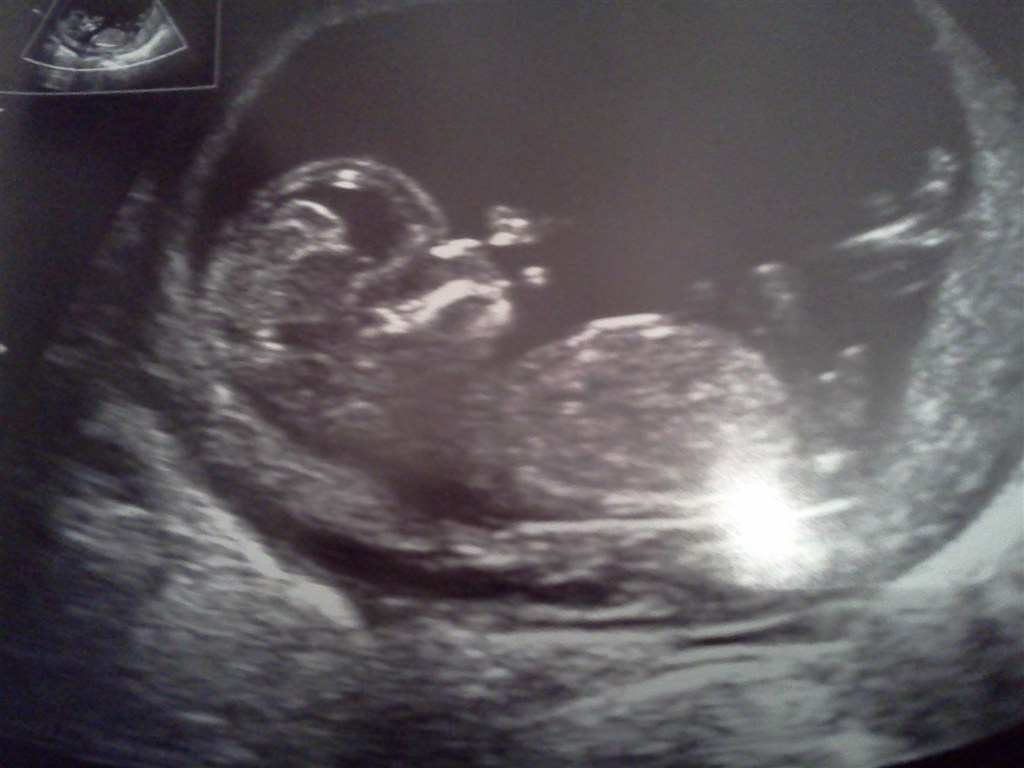

det gik bare rigtig fint.... en lille bandit, som stod op, det har jeg ikke set før... hun prøvede og prøvede , men baby ville bare ikke... så sidste chance inden hun ville scanne indvendigt, var at jeg skulle tømme blæren og hoppe lidt rundt... efter den tur , lykkedes det... wuhuu.. han/hun lagde sig ned... og rutsjede rundt.....pyh ha, hvis han /hun bliver ved med at være så aktiv.....så blir der ikke ro i maven...

vurderingen var 1: 18824 så det var såh fint....

Vedhæftede fotos (klik for at se i fuld størrelse)